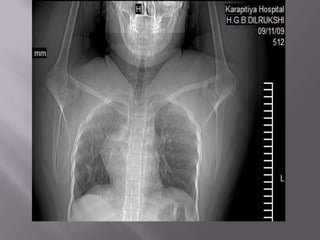

WHAT ARE THE 3 ABNORALITIES?

1). DIFFUSE HYPER DENSITY IN THE LIVER.

(2ry haemachromatosis/transfusional siderosis).

2).MULTIPLE GALLSTONES.

3). SPLENECTOMY.